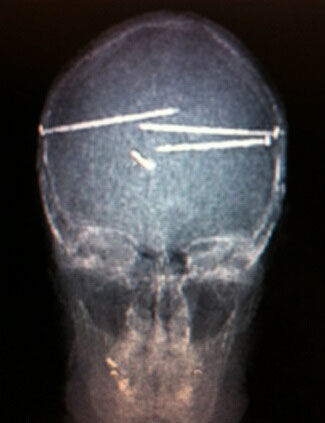

釘打機で自殺を図ろうとしたらしい。

コレ、脳はそれほど損傷を負ってないだろ。

この人は多分、拳銃と同じ様に考えてたんだろう。

実際は違うんだけど。

弾は貫通しない場合、脳ミソをスクランブルエッグみたいに掻き回す。

でも釘は貫通するだけだもん。

釘は穴を開けて内容物を押すだけ。

弾は貫通しながら色々と・・・ね。

脳を貫通したって、基本的には生き延びるぞ。

最終的に22発打ち込んだ。

で、長時間に及ぶ手術の結果、5本残した後に大きなプレートを脳内にはめ込んで終了。

医師が言うには「生命に危険が及ぶ為、残りの5本は抜けなかった」って。

そのX線画像はこんなもんじゃないよ。

Nurse friend sent me this..Guy tried to commit suicide with a nail gun